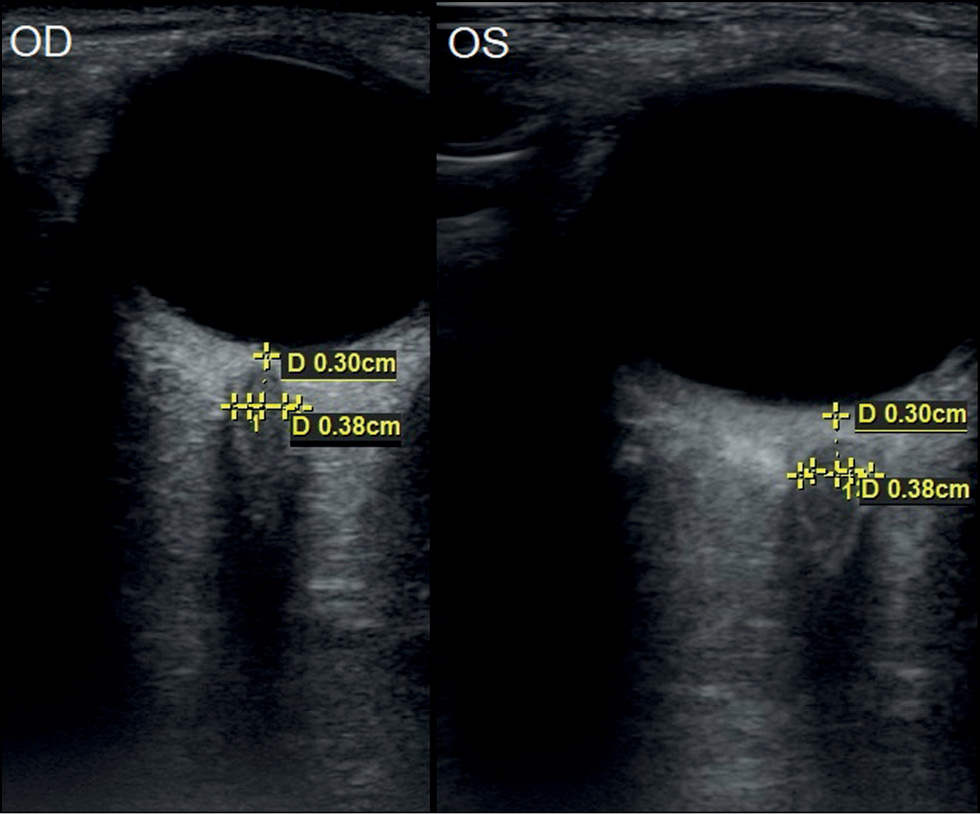

Анализ акустических биометрических параметров зрительного нерва в орбите у 50 здоровых детей (100 глаз) в группе контроля показал, что средние значения толщины нерва составили в 1-й группе 3,78±0,1 мм, во 2-й группе — 4,26±0,06 мм и в 3-й группе — 4,19±0,09 мм (рис. 1, 2). Сравнительная оценка параметров толщины зрительного нерва в разных возрастных группах показала статистически достоверное увеличение средних значений ТОЗН с возрастом ребенка (р <0,05) (табл. 1).

Рис. 1. Эхограмма зрительных нервов в норме у мальчика в возрасте 1 год 3 мес. Данные биометрии ретробульбарного отдела зрительного нерва правого (OD) и левого (OS) глаза.

Fig. 1. Echogram of the optic nerves of a healthy boy aged 15 months and biometric data of the retrobulbar optic nerve of the right (OD) and left (OS) eyes.